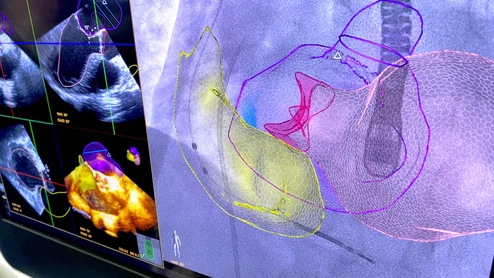

American Society of Echocardiography (ASE) President David H. Wiener, MD, FACC, FAHA, FASE, director of clinical operations at the Jefferson Heart Institute, and a clinical professor of medicine at Thomas Jefferson University, explains the growing number of multimodality cardiac imaging experts and how imaging societies need to change to meet their needs.

ASE President David Wiener detailed some of the many ways imaging societies need to adapt now that so many imagers are specializing in multiple modalities. It may be time to change how annual conferences are scheduled, for example, so that the costs of travel are easier to manage.